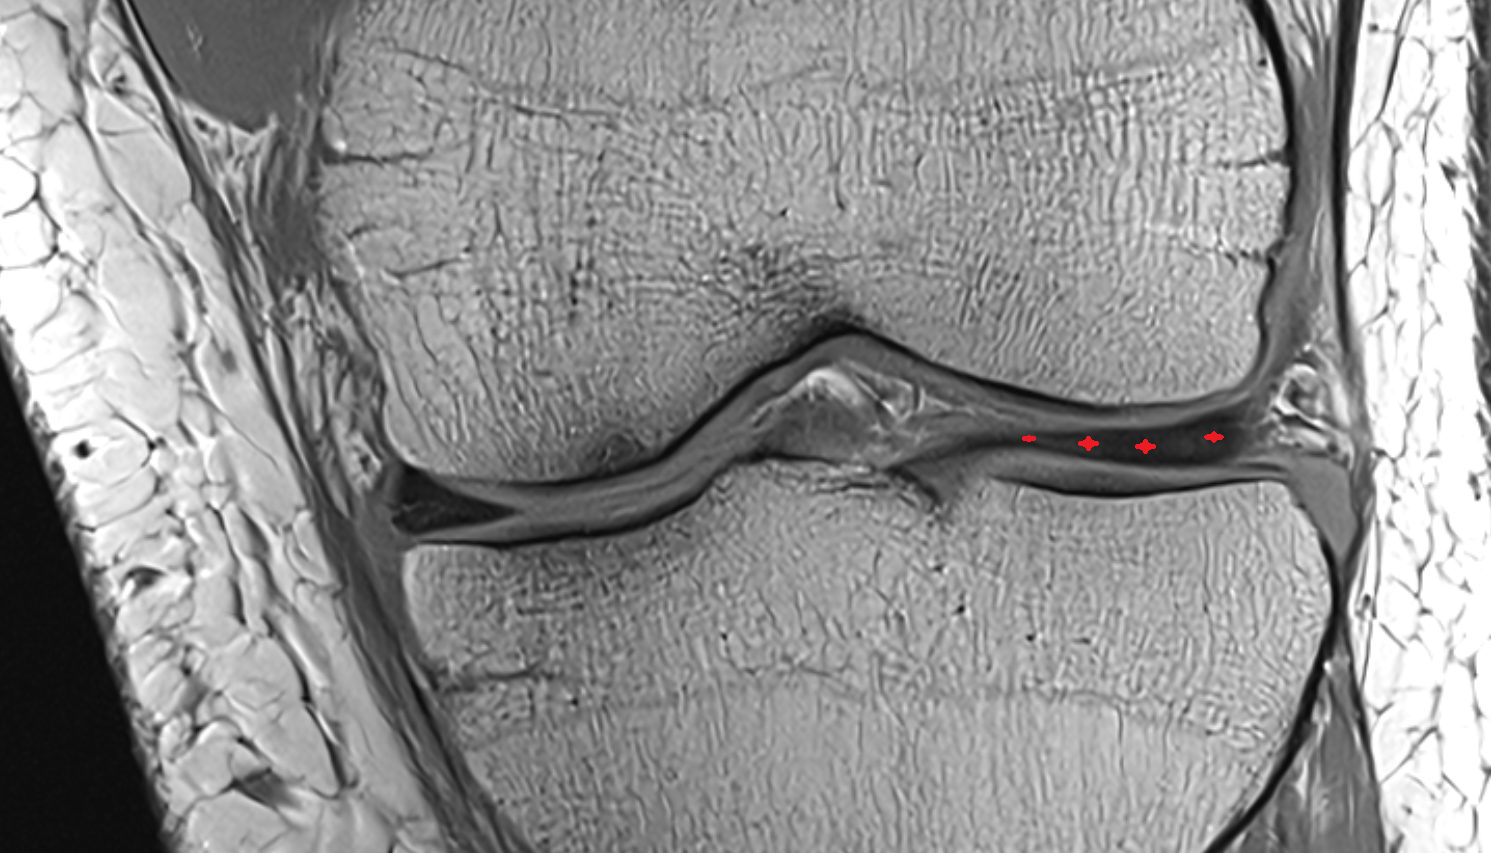

- Medial collateral ligament

- Medial meniscus

- Lateral meniscus

- Anterior horn of medial meniscus

- Posterior horn of medial meniscus

- Body of medial meniscus

- Anterior root of medial meniscus

- Posterior root of medial meniscus